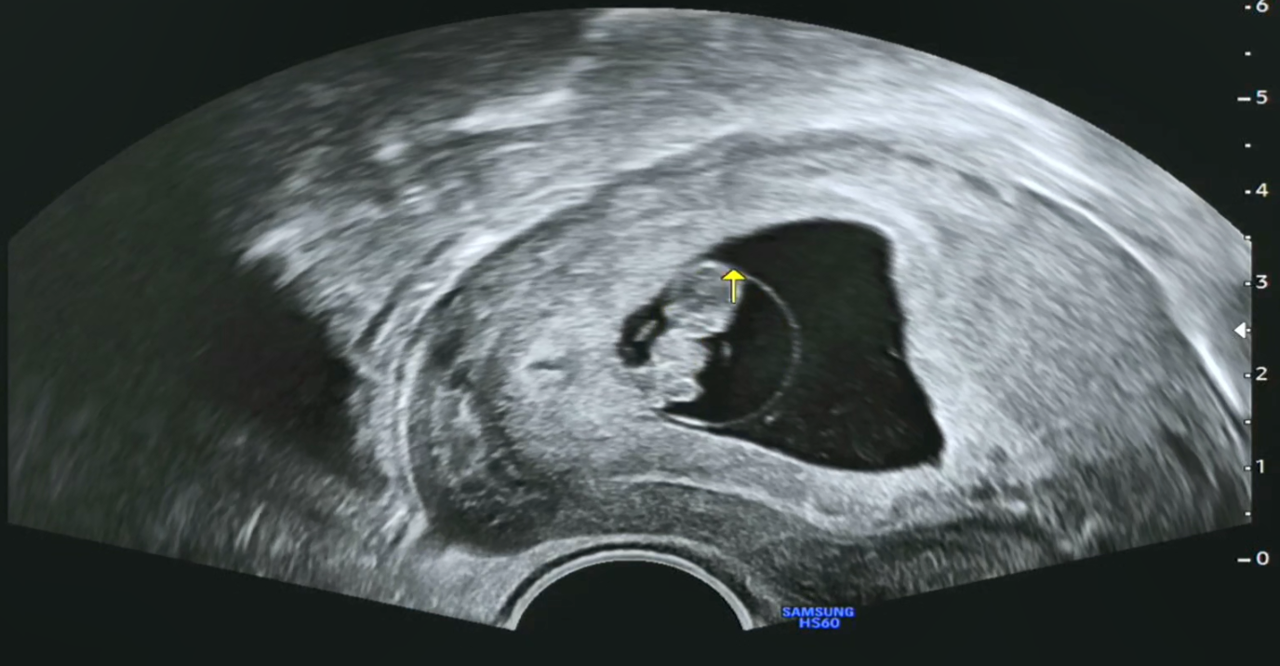

오전 10시쯤 되니 딸아이로부터 카톡을 통해, 우리 '팡팡이의 8주 0일 초음파' 동영상이 날아왔습니다.

임신 7~8주쯤 되면 기관의 형성기라고 해서 아기의 뇌와 몸의 기초가 만들어진다고 하고, 심장이 형성되면서 혈액이 몸으로 보내지기 때문에 심장을 확인할 수 있다고도 하네요.

그리고 이때쯤 되면 머리와 몸의 크기가 같은 2등신이 되고 손발이 구별된다고 해서, 영상을 한번 캡처해 보았습니다. 제가 딸보고 머리가 크다고 했더니 '하리○ 젤리곰' 같다고 하네요. 언듯 보면 '겨울왕국의 올라프' 같이 보이기도 합니다. 태명이 '울라프'도 괜찮아 보이네요.

[팡팡이 8주 차 초음파 영상]